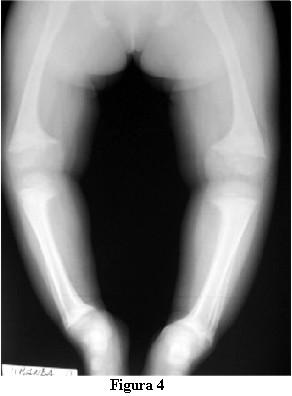

Las radiografías óseas mostraron una descalcificación global, los huesos largos incurvados y ensanchamiento de las metáfisis de los mismos en forma de copa (figuras 2 y 3).

En la evolución a los 3 meses de iniciado el tratamiento con calcitriol, a los 2 años y 9 meses, la marcha tiene las dificultades derivadas de las deformaciones de los miembros pero no presenta caídas, ni fatigabilidad, ni sudoración. La talla es de 81 cm , por debajo del percentil 3. La velocidad del crecimiento de los últimos 3 meses es de 8 cm/año. La fontanela anterior está completamente cerrada.Las radiografías óseas (figuras 4 y 5) muestran, a pesar del corto tiempo de evolución, una disminución del signo de la copa, con un progreso de la diáfisis hacia el tejido osteoide.